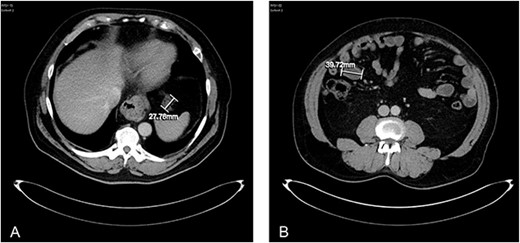

About 1 year later, the patient re-presented for anaemia and underwent a further CT scan. In the right iliac fossa, a 51.96 mm mass was noted such that the appendix could not be visualized separately, with a focus of calcification (Fig. 1). There was infiltration into the adjacent fat and abnormal soft tissue thickening of the peritoneal reflection along the right paracolic gutter. Multiple new peritoneal nodules in the upper abdomen were also identified (Fig. 2). The appearances were in keeping with disseminated malignancy. Following histological analysis, diagnoses of LAMN and PMP was made. The patient was initiated on mitomycin and capecitabine chemotherapy, which modestly reduced the size of the right iliac fossa mass from 51.96 mm to 44.23 mm (Fig. 3).

Three-month post-chemotherapy coronal CT abdomen and pelvis with contrast demonstrating a reduction in size of the primary appendiceal mass to 44.23 mm.